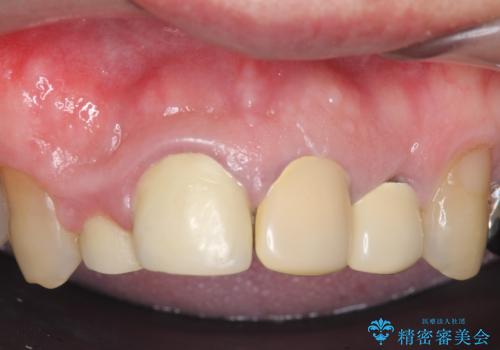

- 前歯の見た目が気になるといらっしゃった方の症例です。

再根管治療後、オールセラミッククラウンによる補綴を行いました。

右上2は歯茎のラインを整えるため歯周外科を行っております。